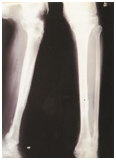

Figure 2: Case 2

1. Infected non union right lower tibia.

2. Radiograph of right tibia fibula with Ilizarov in situ (2nd Post-op).

3. Radiograph of right tibia fibula with Ilizarov in situ after 6 months follow up.

4. Final radiograph of tibia fibula after 8 months follow up.

5. Clinical appearance of the patient (Standing position).

6. Clinical appearance of the patient (sitting position).